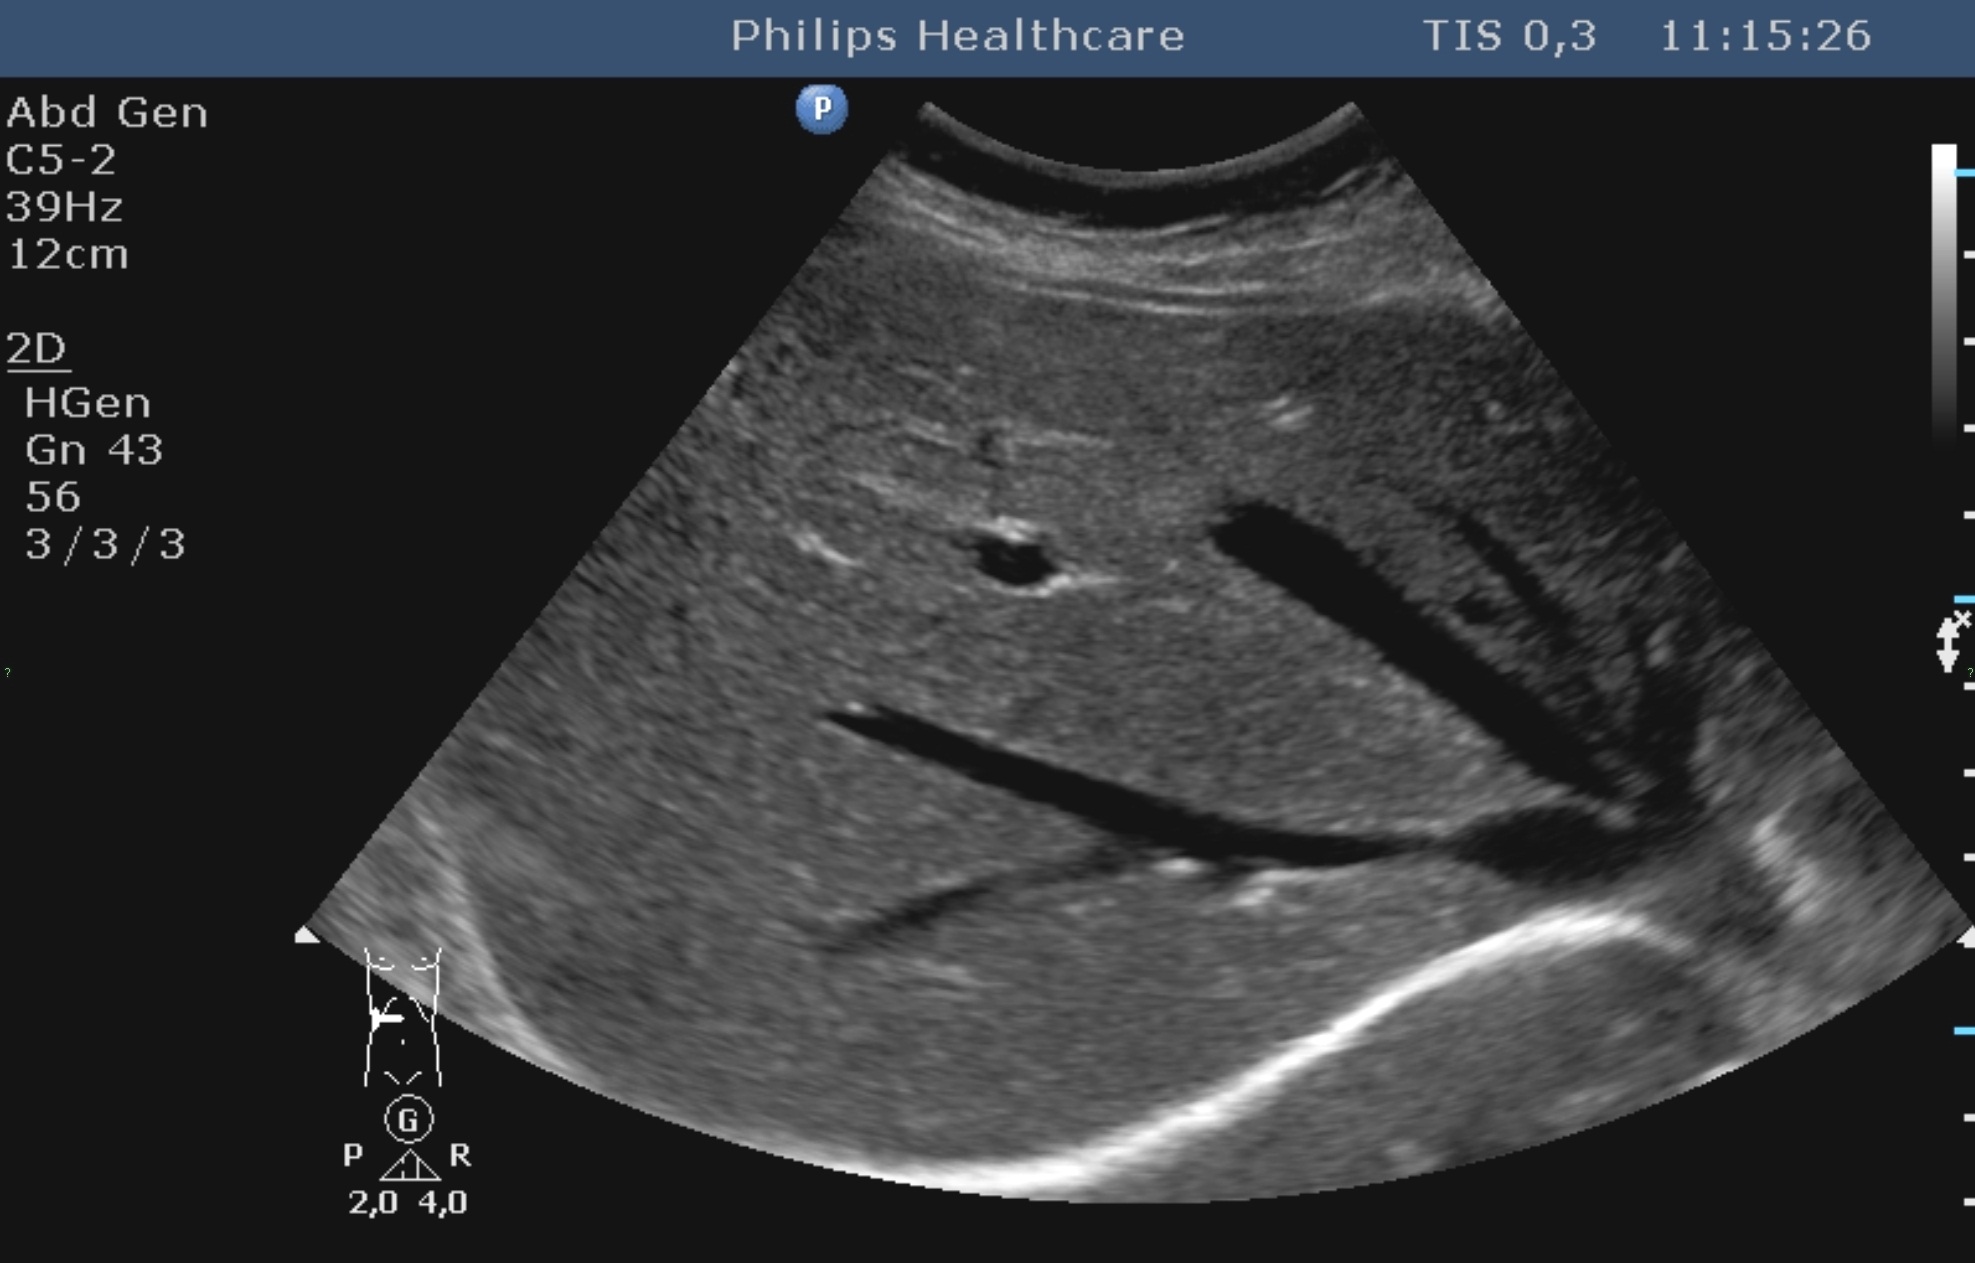

The bacteria may pile up in the biliary ducts due to the bile stasis (either by tumorous or inflammatory choledochus compression) and cholangitis can develop, associated with an abscess development later (Figure 29).

Figure 29: Abscess in the liver, US

In order to prevent it – by either endoscopically or percutaneously – the primary goal is to ensure the bile flow again, obviously completed with broad-spectrum antibiotics.

Liver abscess can develop either following the severe inflammation of the biliary ducts and the gallbladder or following a tumorous necrosis or by the spread of an external inflammation to the liver. By the help of the US, a cystic lesion can be seen with multiple internal echos containing gas bubble frequently as well. In order to determinate the further therapy, contrast enhanced CT examination can be needed, if the US imaging of the entire liver was not possible. An avascular intrahepatic lesion can be seen well on the CT with a contrast enhancing wall (sometimes multifocal as well) (Figure 30). An US or CT guided percutaneous drainage can provide a therapeutic result depending on the lesion's size and location (Figure 31).

Figure 30: Abscess in the liver, native CT

Figure 31: Abscess in the liver, US control after US guided drainage